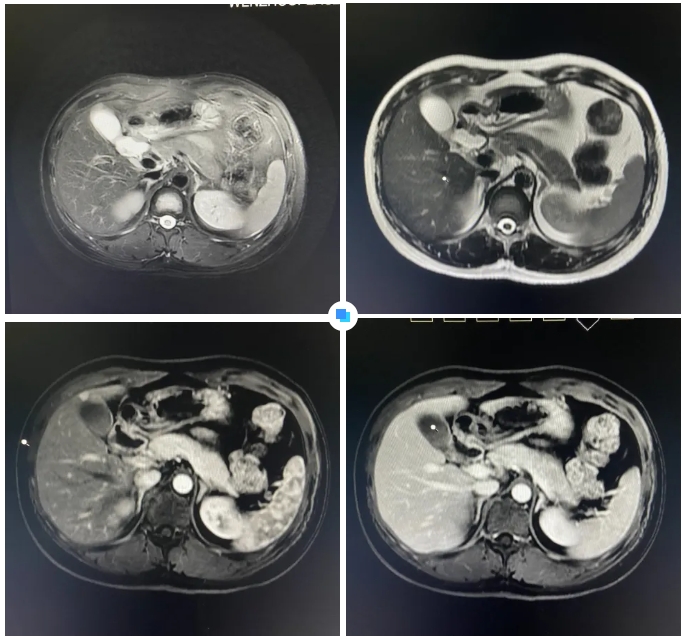

在被問(wèn)到如何發(fā)現(xiàn)隱藏如此深的病灶時(shí),和平國(guó)際醫(yī)院影像中心執(zhí)行主任侯文杰講到,該病灶在平掃T1、T2項(xiàng)都非常不清楚,只有彌散加權(quán)的情況下,病灶區(qū)域顯示出輕微的高信號(hào),這一細(xì)微線索引起了他的高度關(guān)注。

隨后的增強(qiáng)核磁掃描發(fā)現(xiàn),在動(dòng)脈期病灶顯著強(qiáng)化,而在門脈期明顯減退,這一特征與微小肝癌的表現(xiàn)高度吻合。